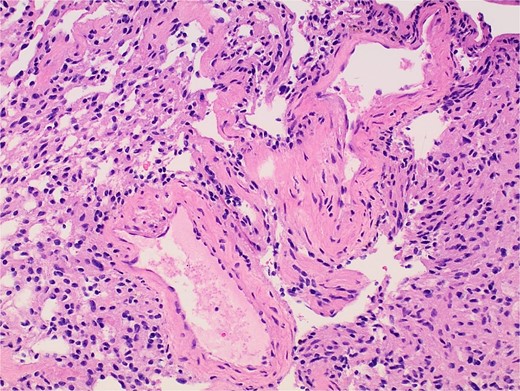

Gross examination and cut sections revealed fragments of tan–white to tan–yellow tissue with some areas of hemorrhage measuring from 1.1 to 3.6 cm in the greatest dimension. Histopathological examination of the excised mass confirmed the diagnosis of a retroperitoneal schwannoma, characterized by S100 positivity (Fig. 3) and degenerative changes, including hemorrhage, hemosiderin, and cystic degeneration (Fig. 4), nuclear atypia (Fig. 5), and perivascular hyalinization (Fig. 6).

Photomicrograph of diagnostic histopathology showing thickened blood vessel walls with hyalinization.